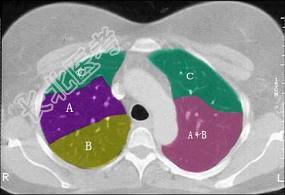

- 单项选择题结合肺段模式(见图),选出右肺下叶的组成 ( )

A、F

B、F+G

C、F+G+H

D、F+G+H+I

E、F+G+H+I+J